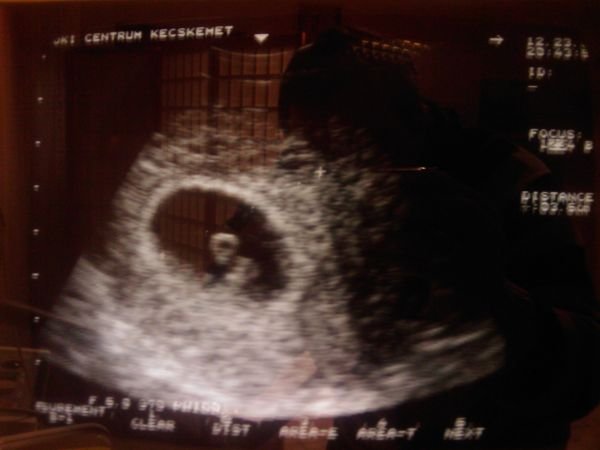

Anettoo: a táblázatba időpontot még nem tudok mondani, de a 13. heti uh lesz nekem a köv. vizsgálat. Még kb. 3 hét... Milyen sok idő! De addigra már 200 nap alá megy a várakozási időm - és a babóka sötétben töltött ideje...